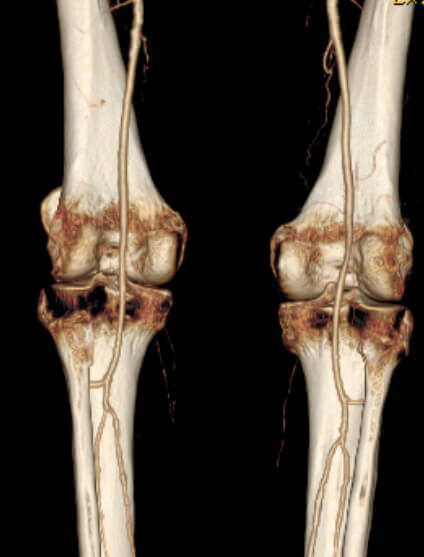

В основе КТ коленного сустава лежит рентгеновское излучение, которое поглощается тканями в зависимости от их плотности. Фактически, такая диагностика является современной разновидностью рентгена. Но способы сбора данных и их обработки существенно отличаются.

Исследуемая область сканируется послойно. Ткани под воздействием пучка рентгеновских лучей по-разному реагируют на облучение. Эти данные фиксируются высокоточным оборудованием, благодаря чему получается трехмерное изображение.

Компьютерная томография коленного сустава позволяет получить трехмерную модель обследуемой области и изображения срезов. Такая диагностика назначается, когда требуется оценить изменения костных структур.

Благодаря КТ коленного сустава можно определить наличие:

- переломов, вывихов, трещин, отломков костей;

- врожденной болезни;

- уплотнений, остеофитов, неровностей, наростов;

- величины суставной щели;

- костных опухолей;

- крови или выпота в полостях.

Часто КТ проводится для подтверждения предварительного диагноза, поставленного после УЗИ или рентгена. Фактически КТ можно назвать современным рентгеном с более широким спектром возможностей.